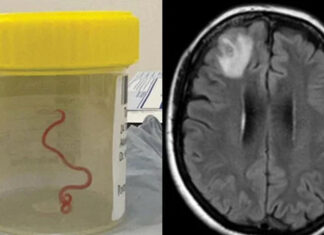

Беспрецедентный случай в медицине: в мозгу женщины нашли живого червя